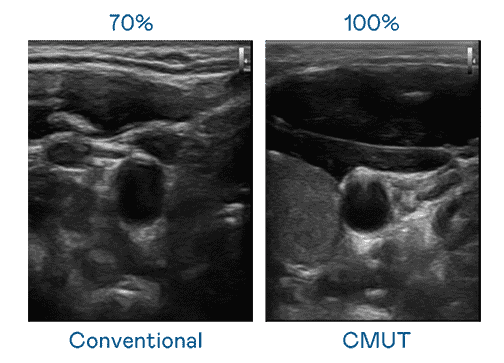

CMUT 技术是一种用电容式微机电元件来产生超音波讯号的技术。。。与传统 PZT 压电式技术相比,,,CMUT 频宽增加 30%,,,,更宽频的超音波讯号让影像解析度大幅提升,,是实现高影像品质医疗超音波扫描、、促进精准医疗发展的关键技术。。。

大频宽带来超清晰影像

超音波影像的解析度高低,,,首先取决于探头能发出的讯号频宽。。2121非凡 CMUT 可提供高清晰的超音波讯号,,,提供高频宽、、高灵敏度、、影像纹理细节更高的超音波影像,,,协助医护人员缩短影像判读时间及利用精准的医疗影像进行诊断。。。。